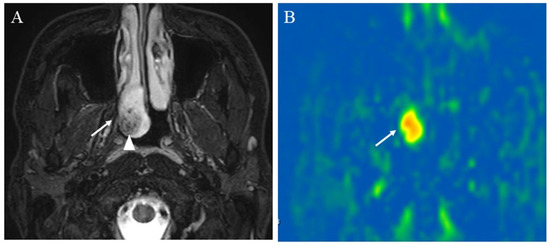

5.1.3. Salivary Gland Tumor Differentiation: Malignant Salivary Tumors, Pleomorphic Adenomas, and Warthin’s Tumors

- Tanaka, F.; Umino, M.; Maeda, M.; Nakayama, R.; Inoue, K.; Kogue, R.; Obara, M.; Sakuma, H. Tumor blood flow and apparent diffusion coefficient histogram analysis for differentiating malignant salivary tumors from pleomorphic adenomas and Warthin’s tumors. Sci. Rep. 2022, 12, 5947. [Google Scholar] [CrossRef]

- Yamamoto, T.; Kimura, H.; Hayashi, K.; Imamura, Y.; Mori, M. Pseudo-continuous arterial spin labeling MR images in Warthin tumors and pleomorphic adenomas of the parotid gland: Qualitative and quantitative analyses and their correlation with histopathologic and DWI and dynamic contrast enhanced MRI findings. Neuroradiology 2018, 60, 803–812. [Google Scholar] [CrossRef]